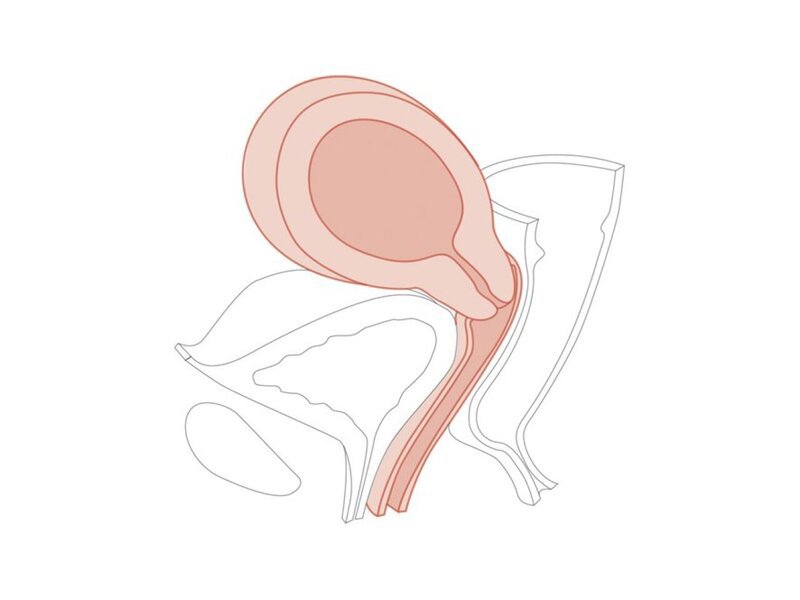

CFPT Mod 6:10-12 weeks Pregnant Cervix

Pregnant Cervix

Clinical Female Pelvic Trainer Mk 3 (CFPT): Module 6

10-12 weeks pregnant module for use with CFPT Mk3 Advanced (LIM-60905) and Standard (LIM-60900).